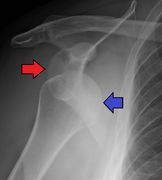

Anterior shoulder dislocation on Y-view